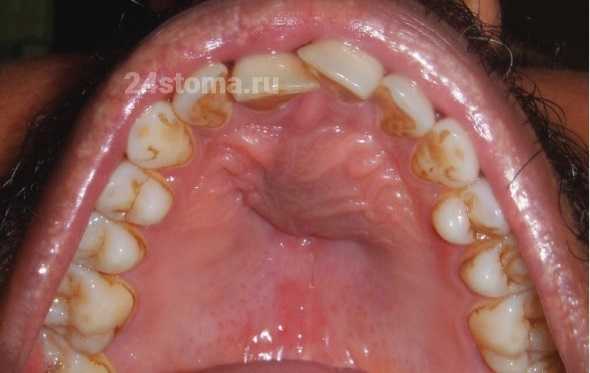

Корневая киста на верхней челюсти (вид в полости рта) –

Обратите внимание, что как в данном случае киста деформировала твердое небо. Такие деформации могут наблюдаться не только на небе, но и с передней стороны альвеолярного отростка верхней и нижней челюсти. Очень часто кисты больших размеров приводят к тому, что происходит полное разрушение костной ткани на передней поверхности альвеолярного отростка челюсти (в проекции корня причинного зуба). И получается так, что под слизистой оболочкой в этом участке будет находиться фиброзная оболочка кисты. В этом случае при пальпации вы не почувствуете твердой кости, палец будет немного проваливаться внутрь.